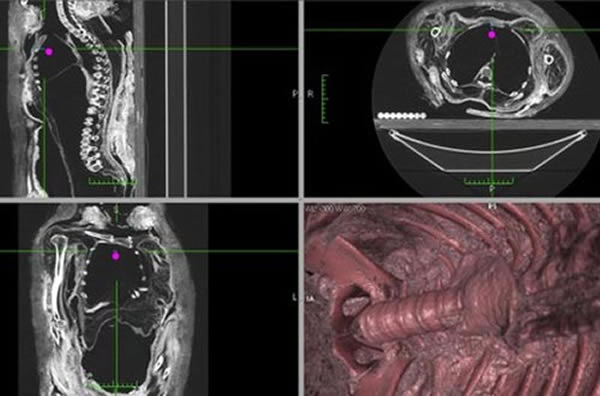

韦德和同事为了检测希罗多德描述的真实性,详细分析了远古埃及150具木乃伊,他们还对7具木乃伊进行CT扫描和3D构造。研究小组发现穷人和富人都通常采用腹切移除内脏的方法,少数贵族成员会在肛门切口移除内脏。同时,并没有大量的证据表明尸体防腐处理时使用香柏油灌肠。

研究人员对加拿大皇家安大略博物馆一具木乃伊尸体空腹体腔进行了CT切片和3D结构重建